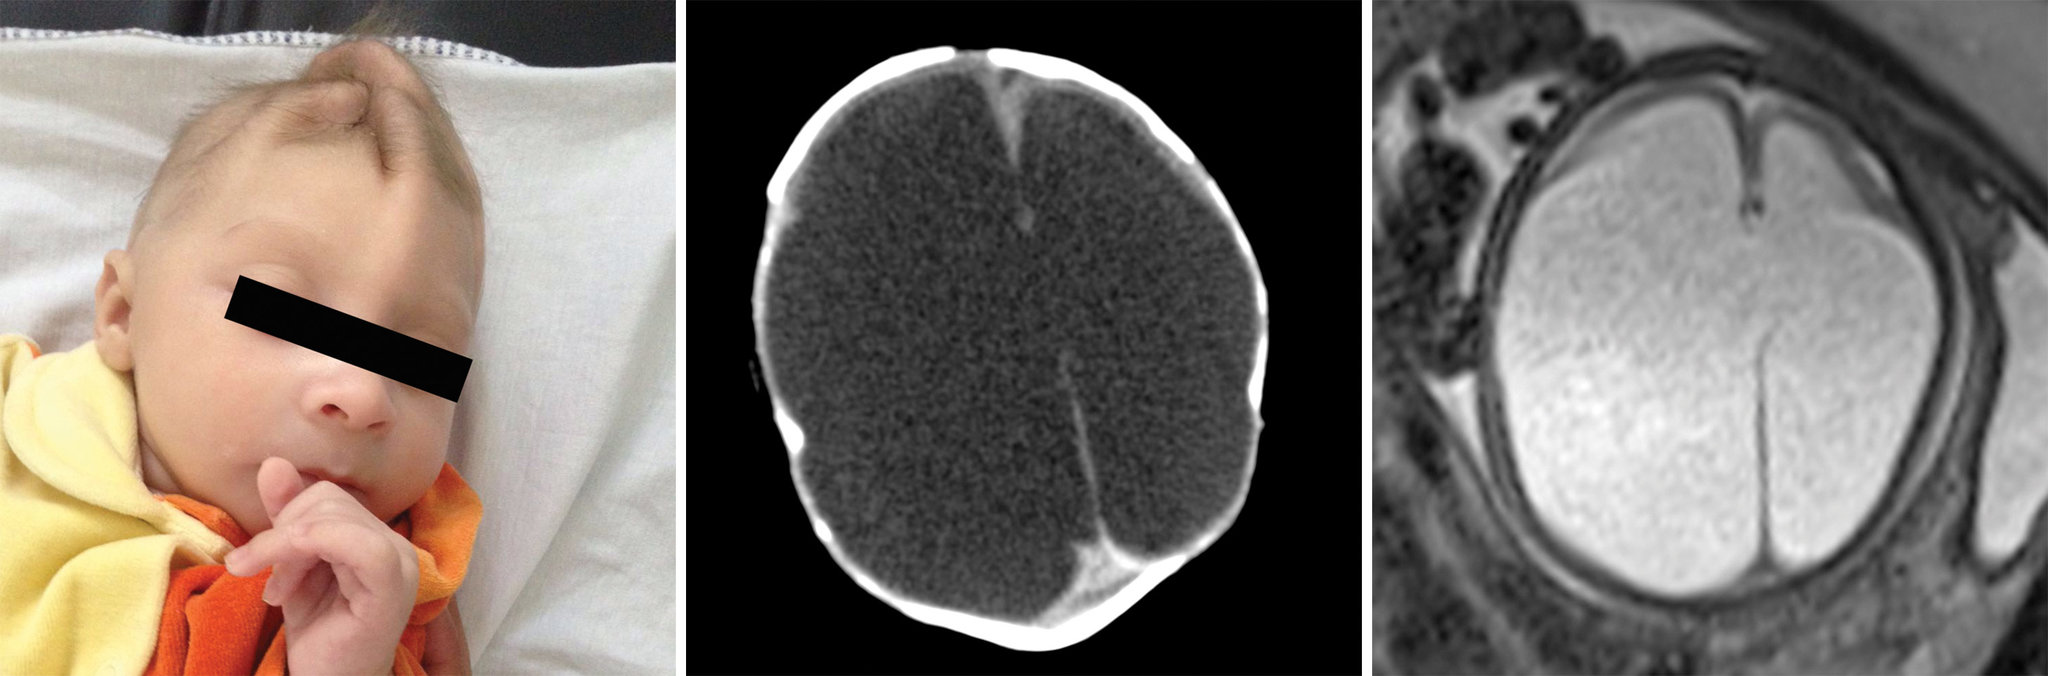

AKIPRESS.COM - The images tell a heartbreaking story: Zika’s calamitous attack on the brains of babies — as seen from the inside, NYTimesreports.

A study of brain scans and ultrasound pictures of 45 Brazilian babies whose mothers were infected with Zika in pregnancy shows that the virus can inflict serious damage to many different parts of the fetal brain beyond microcephaly, the condition of unusually small heads that has become the sinister signature of Zika.

Most of the babies in the study were born with microcephaly, although three were not. Each also suffered other impairments, almost all of which emerge earlier than microcephaly because a smaller head is really a consequence of a brain that has failed to develop fully or has been damaged along the way, experts said.

“The brain that should be there is not there,” said Dr. Deborah Levine, an author of the study and a professor of radiology at Harvard Medical School. “The abnormalities that we see in the brain suggest a very early disruption of the brain development process.”

The scans show the range of Zika’s brain targets, some of which experts knew about, including the corpus callosum, which facilitates communication between the two hemispheres; the cerebellum, which plays a significant role in movement, balance and speech; and the basal ganglia, which are involved in thinking and emotion.